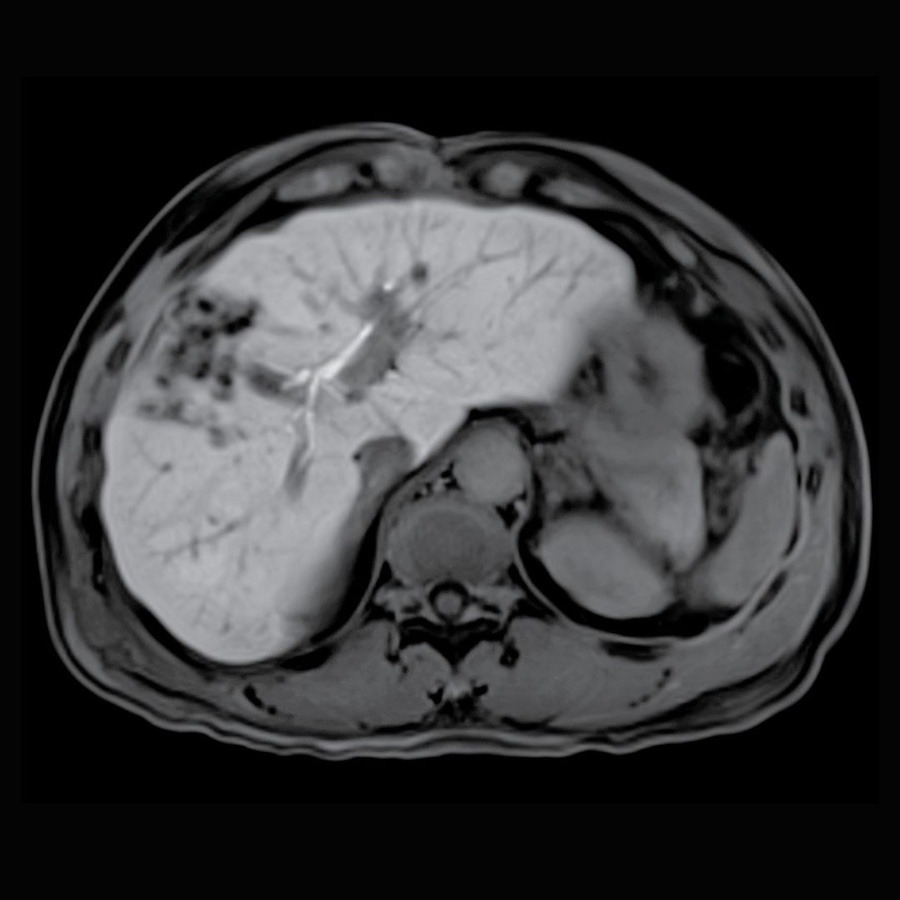

Total Body Imaging

Using 3T MRI technology

Welcome to Kansas City Advanced Diagnostic Imaging Services-Overland Park’s new destination for advanced brain and body imaging. Save time and get the detailed answers you need with our state-of-the-art 3T MRI, featuring 128 channels and a wide bore, which doctors prefer for superior structural detail. We also offer functional imaging for advanced neurological and psychiatric diagnostics. Your scans are interpreted by radiologists with extensive expertise in all imaging modalities. At Kansas City Advanced Imaging, our focus is on providing you with clarity, precision, and peace of mind with every scan.

Our advanced imaging systems provide physicians across specialties with the critical insights needed for effective intervention, surgical planning, and treatment tracking.